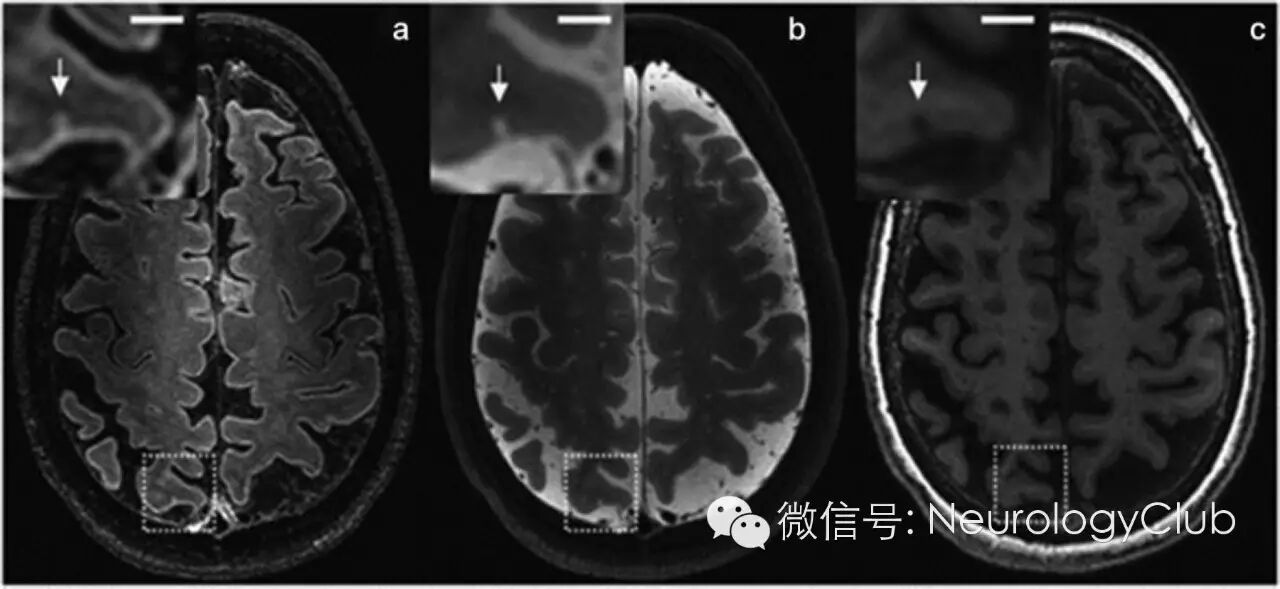

(7.0T磁共振上显示可能的脑微梗死。微梗死在FLAIR[a,0.8×0.8×0.8mm3]和T2WI[b,0.7×0.7×0.7mm3]上为高信号,T1WI[c,1.0×1.0×1.0mm3]上为低信号。比例尺为4mm)